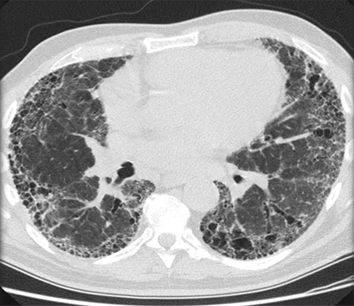

Chest x-ray

A chest x-ray should be obtained early in the evaluation of chronic cough.[38] Although it is not diagnostic of the most common causes, findings may quickly divert the evaluation to causes of greater gravity, such as structural lung diseases. These include lung cancer, pulmonary fibrosis, tuberculosis, bronchiectasis, pneumonia, aspiration, and sarcoidosis.[Figure caption and citation for the preceding image starts]: Chest x-ray showing hyperinflation in a patient with COPD. The hyperinflation is caused by the emphysema component of COPD, rather than the chronic bronchitis that underlies symptoms of coughFrom the personal collection of Dr M. A. Sharifabadand, SUNY at Stony Brook School of Medicine, Department of Pulmonary and Critical Care Medicine, Mineola, New York and Dr J. P. Parsons, The Ohio State University Medical Center, Columbus; used with permission [Citation ends].com.bmj.content.model.assessment.Caption@65a65855[Figure caption and citation for the preceding image starts]: Chest x-ray showing multiple miliary lung metastases (arrows). The primary tumour was a thyroid carcinomaE. Dick, Student BMJ. 2001;9:10-12 [Citation ends].com.bmj.content.model.assessment.Caption@25657fee[Figure caption and citation for the preceding image starts]: Chest x-ray showing left hilar carcinoma (arrow)From: E. Dick, Student BMJ. 2000;8:358-360 [Citation ends].com.bmj.content.model.assessment.Caption@567b9fef[Figure caption and citation for the preceding image starts]: Chest x-ray showing a cavitating right hilar carcinoma (arrow)E. Dick, Student BMJ. 2001;9:10-12 [Citation ends].com.bmj.content.model.assessment.Caption@3d6fa55[Figure caption and citation for the preceding image starts]: Chest x-ray in a patient with bronchogenic carcinoma showing a left-sided pleural effusionFrom: R. Thakkar, Student BMJ. 2001;9:458 [Citation ends].com.bmj.content.model.assessment.Caption@5b46acec[Figure caption and citation for the preceding image starts]: Chest x-ray showing interstitial fibrosis in a patient with amiodarone pulmonary toxicityFrom the personal collection of Dr A. Pataka and Professor P. Argyropoulou, Aristotle University, Thessaloniki, Greece; used with permission [Citation ends].com.bmj.content.model.assessment.Caption@2c3c94b0[Figure caption and citation for the preceding image starts]: Chest x-ray showing pulmonary tuberculosis with cavitationFrom the personal collection of Dr M. Narita, Department of Pulmonary and Critical Care Medicine, University of Washington [Citation ends].com.bmj.content.model.assessment.Caption@3dd7f84b[Figure caption and citation for the preceding image starts]: Chest x-ray showing multiple discrete nodules throughout both lungs (one of which is circled) in a patient with miliary tuberculosisE. Dick, Student BMJ. 2001;9:10-12 [Citation ends].com.bmj.content.model.assessment.Caption@23fa6365[Figure caption and citation for the preceding image starts]: Chest x-ray with lack of normal tapering producing a tram line in a patient with bronchiectasisFrom the personal collection of Dr S.M. Bhorade, University of Chicago Medical Center; used with permission [Citation ends].com.bmj.content.model.assessment.Caption@36b415f2[Figure caption and citation for the preceding image starts]: Chest x-ray with dilated and thickened airways in a patient with bronchiectasisFrom the personal collection of Dr S.M. Bhorade, University of Chicago Medical Center; used with permission [Citation ends].com.bmj.content.model.assessment.Caption@78e208fa[Figure caption and citation for the preceding image starts]: Chest x-ray showing increased opacification of the right perihilar region and superior segment of the right lower and upper lobes consistent with worsening aspiration pneumoniaFrom the personal collection of Dr R. Kanner, University of Utah School of Medicine [Citation ends].com.bmj.content.model.assessment.Caption@71be2c1f[Figure caption and citation for the preceding image starts]: Portable chest x-ray with bibasilar opacities, worse on the right than the left, in a patient with hospital-acquired pneumoniaFrom the personal collection of Dr F. W. Arnold, Division of Infectious Diseases, Department of Medicine, University of Louisville School of Medicine [Citation ends].com.bmj.content.model.assessment.Caption@2c704497[Figure caption and citation for the preceding image starts]: Chest x-ray showing early ill-defined opacities of the right upper lobe above the minor fissure consistent with early changes of aspiration pneumoniaFrom the personal collection of Dr R. Kanner, University of Utah School of Medicine [Citation ends].com.bmj.content.model.assessment.Caption@23fa54d0[Figure caption and citation for the preceding image starts]: A. Portable upright chest x-ray before aspiration; B. Chest x-ray 1 hour after aspiration, showing bilateral diffuse alveolar infiltrates, worse at the bases on the right sideFrom the personal collection of Dr S. Murgu and Dr H. Colt, University of California at Irvine Medical Center [Citation ends].com.bmj.content.model.assessment.Caption@7860be3a[Figure caption and citation for the preceding image starts]: Chest x-ray showing bilateral hilar adenopathy in a patient with sarcoidosisFrom the personal collection of Dr M.P. Muthiah, Division of Pulmonary and Critical Care and Sleep Medicine, University of Tennessee [Citation ends].com.bmj.content.model.assessment.Caption@31e94b4e